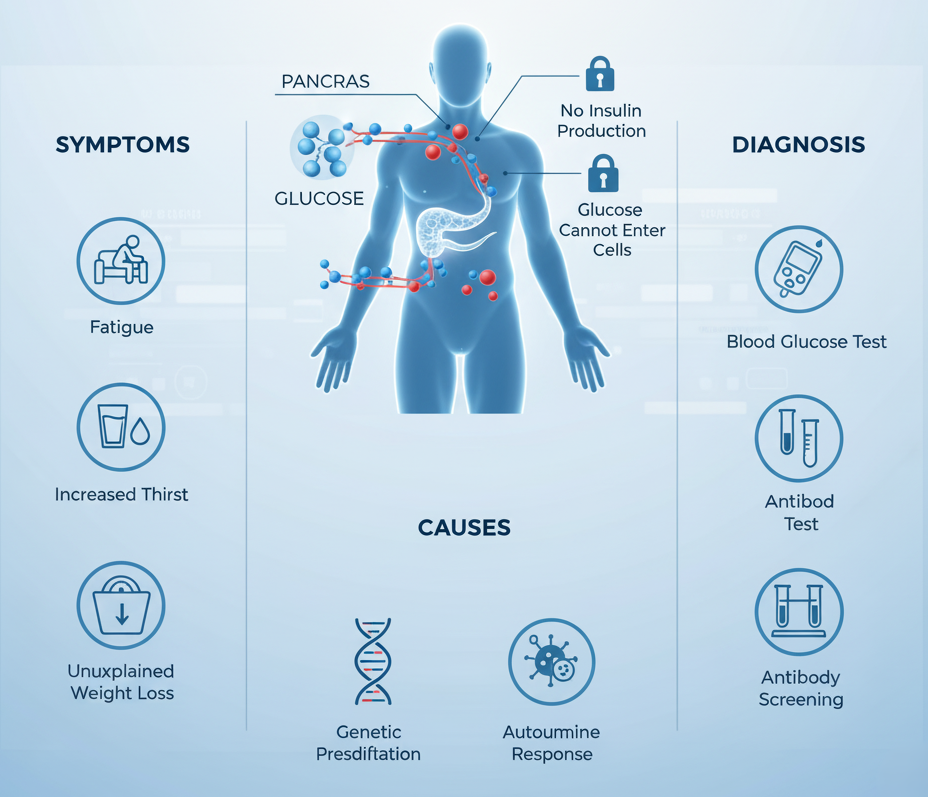

Type 1 Diabetes Explained: Symptoms, Causes, and Diagnosis

It is the chronic condition in which of the body immune system mistakenly attacks the…